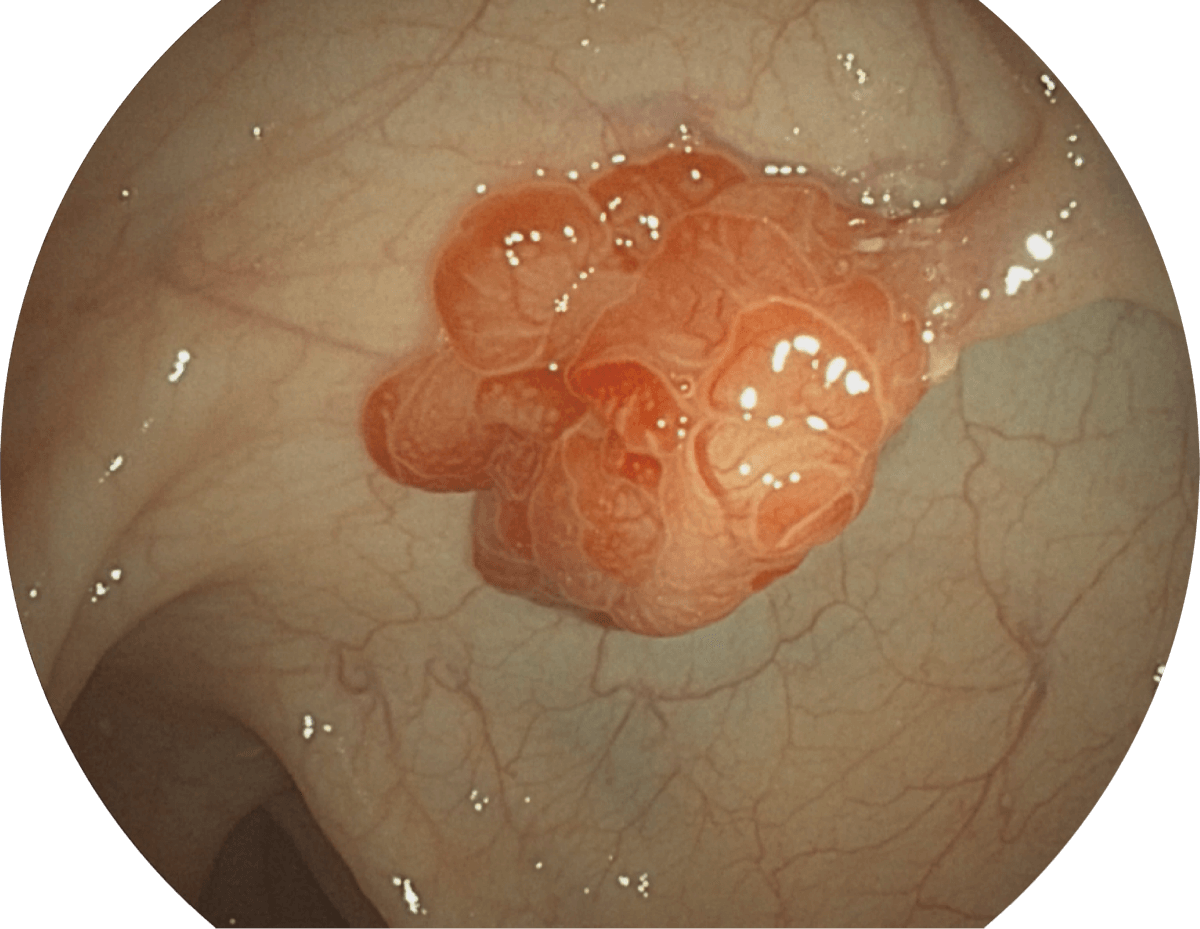

具有聚谱成像技术(SFI)及光电复合染色成像技术(VIST),可完美呈现粘膜细节及病变特征。

WL